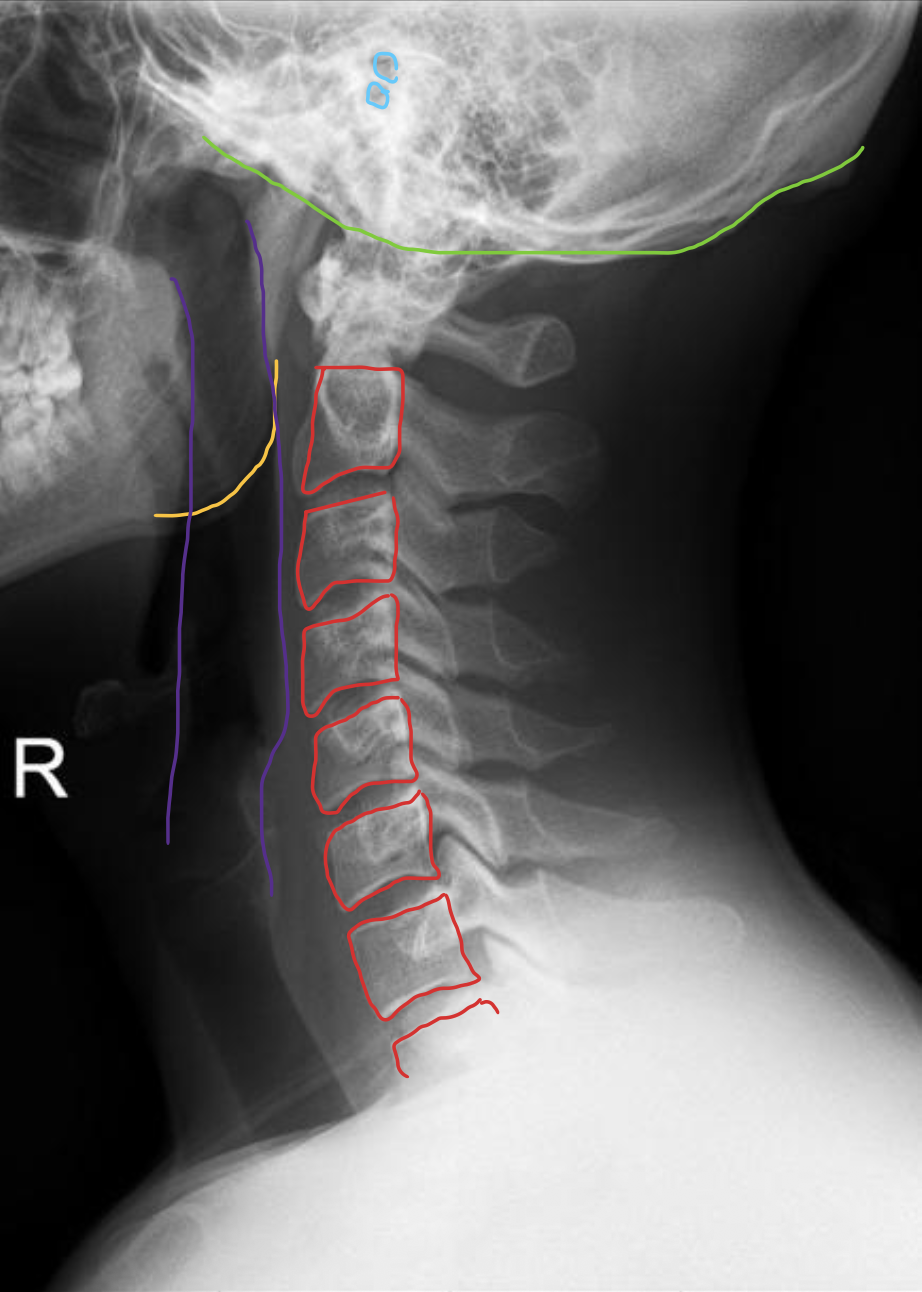

前结节

Anterior tubercle

后结节

Posterior tubercle

椎弓根

Pedicle

椎动脉

Vertebral artery

气管

Trachea

胸锁乳突肌

Sternocleidomastoid

颈内静脉

Jugular vein

颈动脉

Carotid artery

蛛网膜下腔

Subarachnoid space

脊髓

Spinal cord

前纵韧带

Anterior longitudinal ligament (ALL)

后纵韧带

Posterior longitudinal ligament (PLL)

颈深筋膜

Cervical fascia

棘间韧带

Interspinales

T1

T2